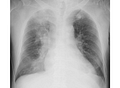

pulmonary consolidation

Hội chứng đông đặc phổi là tình trạng nhu mô phổi bị xốp, một vùng phổi bị tăng tỷ trọng nên dễ bị tổn thương, sưng viêm hơn.

Hội chứng đông đặc phổi dễ dàng nhận thấy nhất trên phim chụp X-quang.

Pulmonary consolidation is most easily seen on an X-ray.